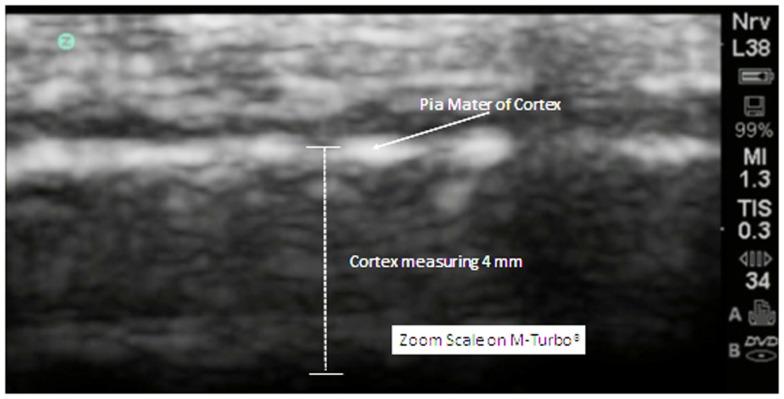

Comparisons of the extra-axial spaces indicated increases in the ASD subjects. For EAF we scored based on the gyral summit distances between the arachnoid membrane and the cortical pia layer (subarachnoid space): (1) <0.05 cm, (2) 0.05-0.07 cm, (3) 0.08-0.10 cm, (4) >0.10 cm. All of the neurotypical siblings scored 1, whereas the ASD mean score was 3.41 ± 0.67. We also defined cortical dysplasia as the following: hypoechoic lesions within the substance of the cortex, or disturbed layering within the gray matter. For cortical dysplasia we scored: (1) none observed, (2) rare hypoechogenic lesions and/or mildly atypical cortical layering patterns, (3) more common, but separated areas of cortical hypoechogenic lesions, (4) very common or confluent areas of cortical hypoechogenicity. Again all of the neurotypical siblings scored 1, while the ASD subjects' mean score was 2.79 ± 0.93.

对额外轴外空间的比较表明 ASD 受试者的空间增加。对于 EAF,我们根据蛛网膜膜和皮质软脑膜层之间的脑回峰距进行评分(亚蛛网膜空间):(1)<0.05cm,(2)0.05-0.07cm,(3)0.08-0.10cm,(4)>0.10cm。所有神经典型的兄弟姐妹均得分为 1,而 ASD 的平均得分为 3.41±0.67。我们还将皮质发育不良定义为以下情况:皮质实质内的低回声病变,或灰质内的分层紊乱。对于皮质发育不良,我们评分:(1)无观察到,(2)罕见的低回声病变和/或皮质分层模式轻度异常,(3)更常见,但皮质低回声病变分离区域,(4)皮质低回声性非常常见或融合区域。同样,所有神经典型的兄弟姐妹均得分为 1,而 ASD 受试者的平均得分为 2.79±0.93。